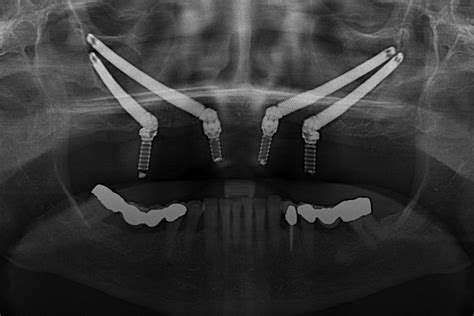

Además, los implantes cigomáticos son una excelente alternativa en casos de pérdida ósea severa en el maxilar superior. Estos implantes se anclan en el hueso cigomático (pómulo), evitando la necesidad de un injerto óseo en el maxilar. Al contrario que los implantes osteointegrados convencionales, que se colocan encima del maxilar, los cigomáticos se insertan en diagonal, en el arco de las mejillas.